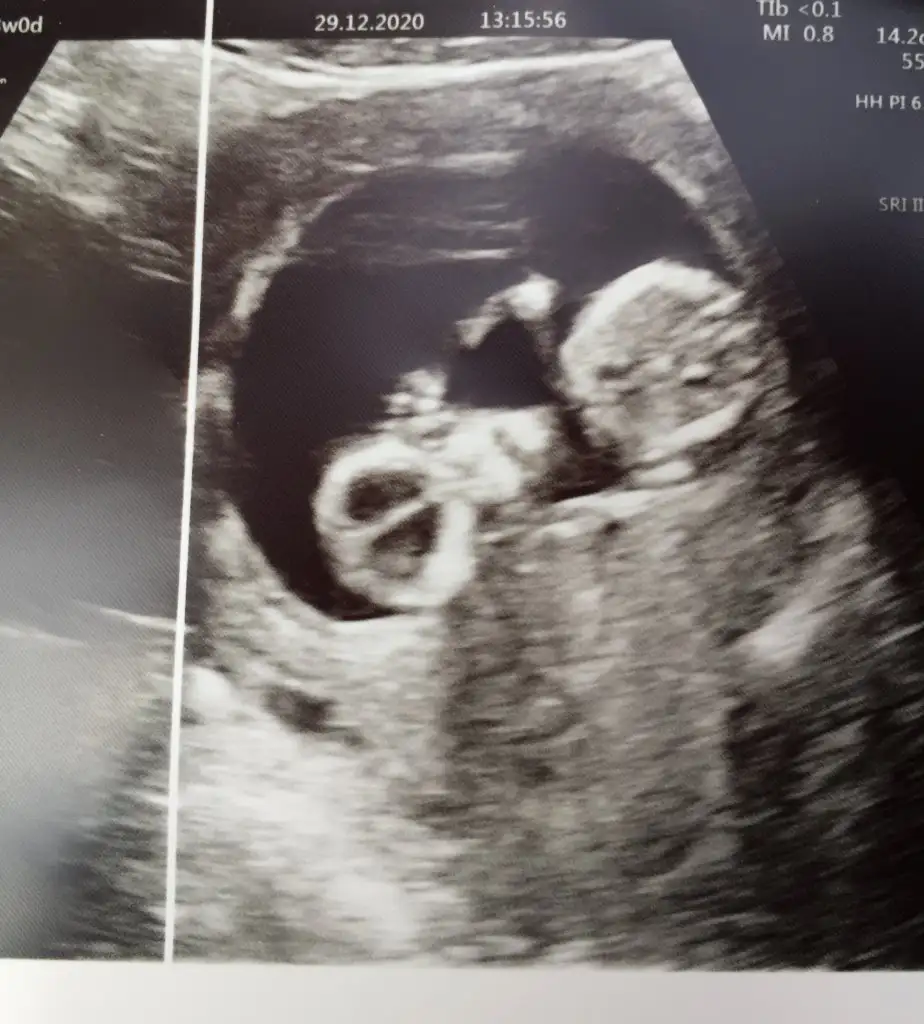

11+3 aslında ama 13te gidersem yine atarım canım 7. Haftaya kız demiştin hadi bakalım sağlıklı akıllı bebisler olsunlar da inşallahBebek baş aşağı yorum nasıl yapacam şaşırdım11 12 13 haftalar olursa paylaşın erkek gibi sanki bir uzantı var nubunda ama olmayabilir

Öğrendik canım evet Dr %100 erkek dedi 2. Kez oğlum olacak, çok teşekkür ederim sanadaDiğeride emin değildim bu usgde 16 hafta nub olmaz artıkgörünen pipi ise sanki erkek belkide değildir 16 haftadan pek anlamıyorum cnm gönlünüzden geçeni nasip etsin rabbim inşallah ogrenmedinizmi

Pipimi bu yoksa kordonmu emin olamadım ogrendik

Bi tahmin alabilir miyim acabaBoyutsuz olursa daha iyi olur hiç net değil usgde